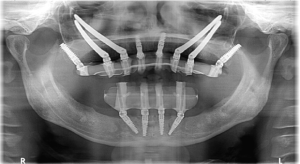

What are the 3 types of dental implants? Discover detailed differences, expert advice, and why Albania is a top destination for implants.